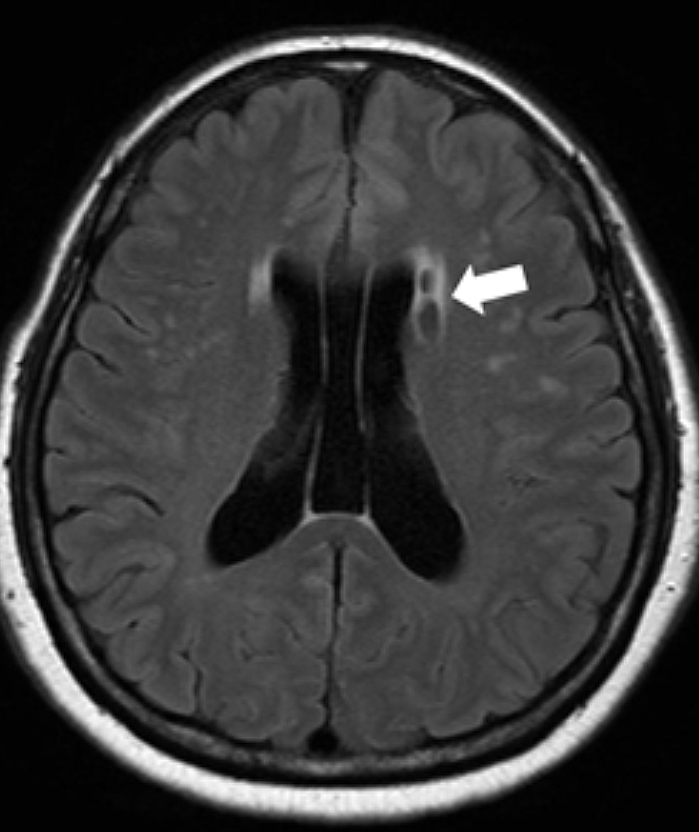

전조증상이 발현되면 뇌졸중 예방과 선제적 치료를 위해 MRI 검사 등 정확한 진단을 받습니다. MRI 검사는 예전과 다르게 뇌질환으로 의심되는 신경학적 증상이 있는 환자는 모두 사비의 부담 없이 뇌질환 예방 검진이 가능하게 되었습니다. 뇌졸중으로 진단받았다면 증상 정도와 환자 상태에 따라 약물치료, 내과적 시술, 외과적 수술을 시행합니다. 최근에는 중재적 시술이 발달해 골든타임안에 내원하면 막힌 혈관 내에 스텐트라는 그물망을 삽입해 혈전을 제거하는 뇌혈관 중재술을 통해 후유증을 줄이며 효과적으로 치료하는 방법도 있습니다.